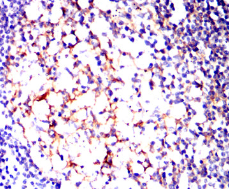

IHC    1/200 - 1/1000